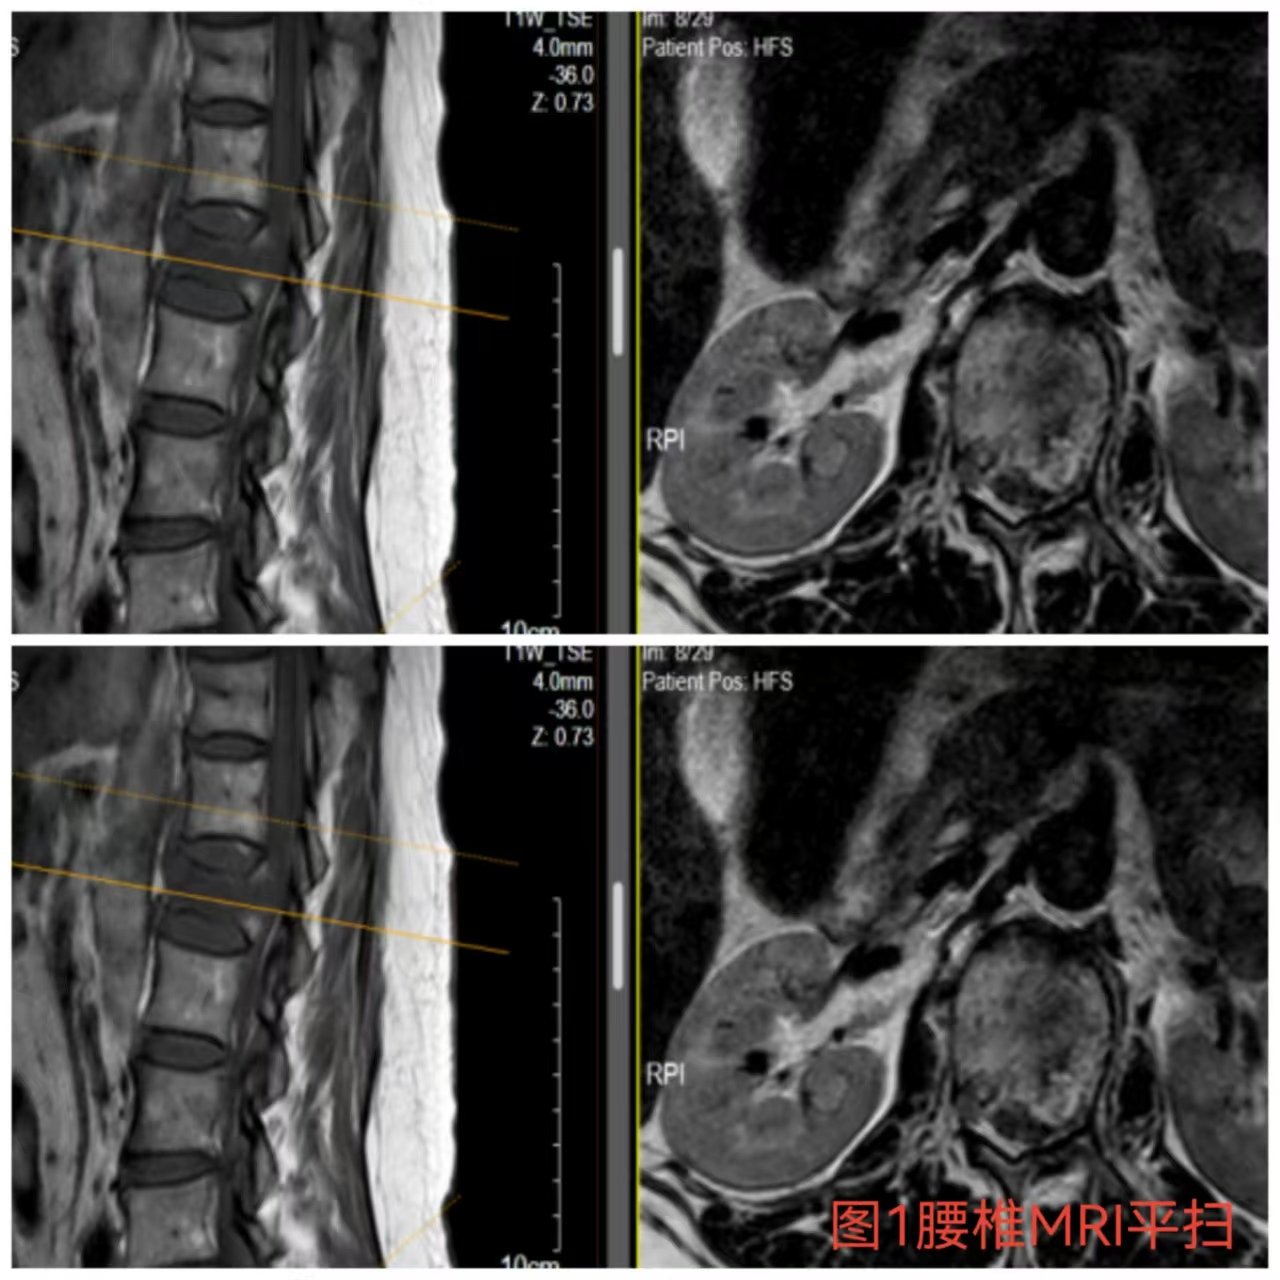

入院時(shí)患者躺在床上不能動(dòng)彈,眼神中透漏著深深的無助,對(duì)于她來說這種傷情無疑是沉重的,尤其是腹股溝以下感覺消失、雙下肢肌力0級(jí),這意味著其下肢無法活動(dòng)及站立,仿佛被命運(yùn)按下了暫停鍵;與病人及家屬充分溝通病情后,第一時(shí)間給予對(duì)癥治療,監(jiān)測(cè)患者生命體征,行腰椎核磁檢查(圖1)提示:腰1椎體爆裂性骨折,椎體后緣塌陷致骨性椎管狹窄,壓迫脊髓神經(jīng),結(jié)合患者病情及輔助檢查可診斷為:“L1椎體爆裂性骨折伴雙下肢截癱”。

俞德亮副主任醫(yī)師深知病情的嚴(yán)重性,拖得時(shí)間越久,脊髓神經(jīng)損傷癥狀越難以恢復(fù),必須把握住早期減壓手術(shù)的關(guān)鍵時(shí)間窗,緊急帶領(lǐng)創(chuàng)傷骨科醫(yī)師團(tuán)隊(duì)對(duì)該病情進(jìn)行討論、制定手術(shù)方案,并成功為患者急診行“L1椎體爆裂性骨折伴截癱切開椎板切除+椎管探查減壓+骨折復(fù)位釘棒系統(tǒng)內(nèi)固定術(shù)(圖2)”,該手術(shù)精確解除對(duì)脊髓神經(jīng)的壓迫,并通過椎弓根螺釘內(nèi)固定系統(tǒng)對(duì)受損的腰椎提供穩(wěn)固的支撐,為后期的康復(fù)創(chuàng)造了良好的條件。